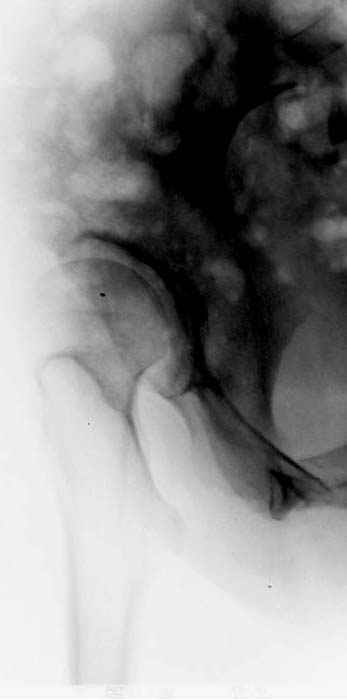

В качестве иллюстрации ограничения приведения бедра связкой головки бедра и/или наклон таза в неопорную сторону в одноопорном ортостатическом положении можно привести схему (Рис.4, где F – сила реакции связки головки бедра, J – сила воздействия нижнего сектора вертлужной впадины на нижне-медиальный сектор головки, Р – вес тела). Согласитесь, что если связка головки бедра нерастяжимый элемент (именно такой и должна быть связка из коллагена) дальнейшее приведение невозможно. Если она удлинена или гиперрастяжима, при дальнейшем приведении дистальный конец связки попадет между суставными поверхностями… (Это одно из наиболее вероятных объяснений известного симптома «блокады» тазобедренного сустава).

Кликните для загрузки файла Рис.4.jpg

54KB (55676 bytes)